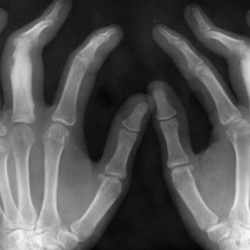

Женщина 30 лет, направлена на R-графию кисти в связи с болями в последней.

Случайная находка состоит в наличии инородных тел мягких и костных тканей области правого запястья. Пациентка длительное время наблюдается у ревматолога по поводу Ревматоидного полиартрита, а про...